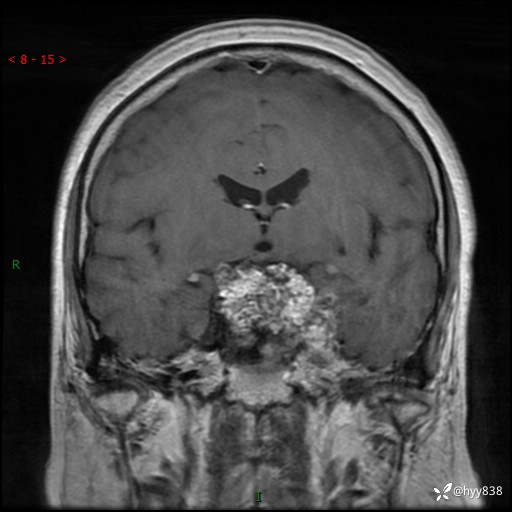

增强 COR +SAG

鞍区MRI平扫

临床诊断:鞍区肿物

治疗经过:手术